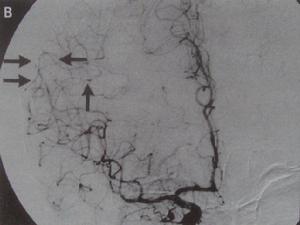

頸內動脈閉塞綜合徵應常規進行CT檢查,多數病例發病24小時後逐漸市低密度梗死灶,發病後2-15日可見均勻片狀或楔形的明顯低密度灶,大面積腦梗死伴腦水腫和占位效應,出血性梗死呈混雜密度,應注意病後2-3周梗死吸收期,病灶水腫消失及吞噬細胞侵潤可與腦組織等密度,CT上難以分辨,稱為“模糊效應”。增強掃描有診斷意義,梗死後5-6日出現增強現象,1-2周最明顯,約90%的梗死灶顯示不均勻的病變組織。但有時CT不能顯示腦幹、小腦較小梗死灶。 MRI可清晰顯示早期缺血性梗死、腦幹及小腦梗死、靜脈竇血栓形成等,梗死後數小時即出現T1低信號、T2高信號灶,出血性梗死顯示其中混雜T1高信號。釓增強MRI較平掃敏感。功能性MRI彌散加權成像(DWI)可早期診斷缺血性卒中,發病2小時內即顯示缺血病變,為早期治療提供重要信息。DSA可發現血管狹窄及閉塞部位,顯示動脈炎、Moyamoya病、動脈瘤和靜脈畸形等。

2)動脈溶拴療法-作為卒中緊急治療,可在DSA直視下進行超選擇介入動脈溶拴。尿激素酶動脈溶拴合用小劑量肝素靜脈滴注,可能對出現症狀3-6小時的大腦中動脈分布區卒中病人有益。